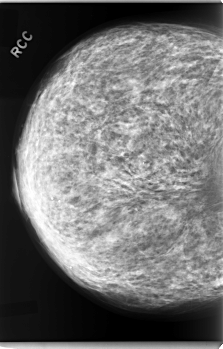

C_0078_1.RIGHT_CC

RIGHT_CC LINES 5920 PIXELS_PER_LINE 3784 BITS_PER_PIXEL 12 RESOLUTION 50 NON_OVERLAY

RIGHT_MLO LINES 5792 PIXELS_PER_LINE 4160 BITS_PER_PIXEL 12 RESOLUTION 50 NON_OVERLAY